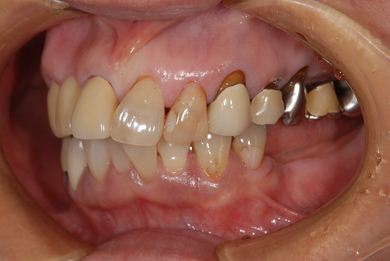

治療前

• 治療前